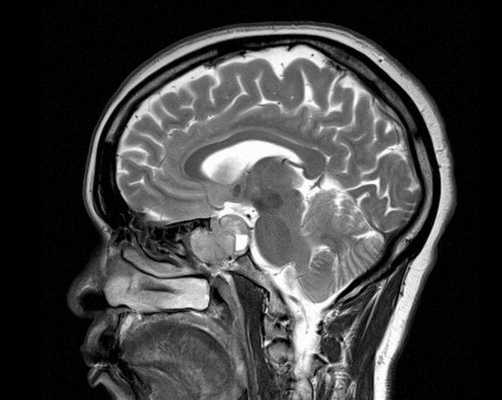

Снимок МРТ головного мозга в двух проекциях